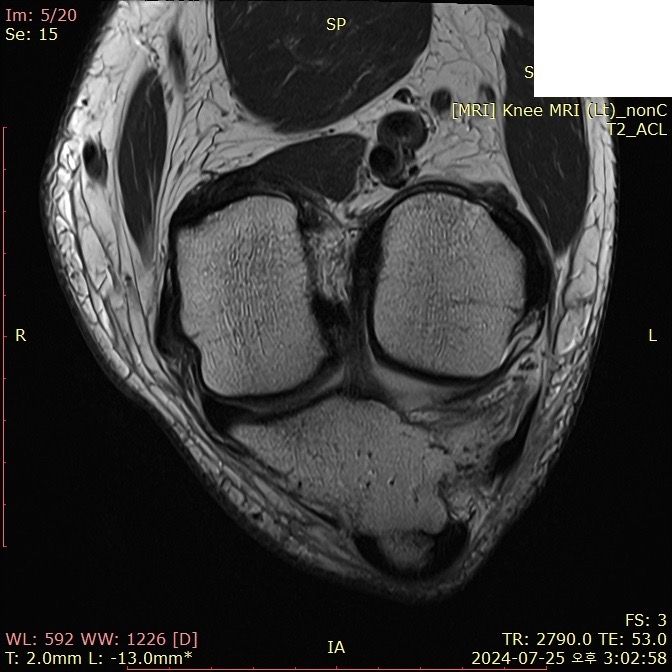

무릎 ACL(전방십자인대) 확인 부탁드려요

아스팔트에 무릎을 부딪쳐 심하게 부어서 mri 찍어봤는데 슬개골 비변위성 골절 판독 받은 건 기억 나는데, 인대는 기억이 잘 안나서 여쭤 봅니다..

전방십자인대 괜찮은가요...??ㅠㅠ